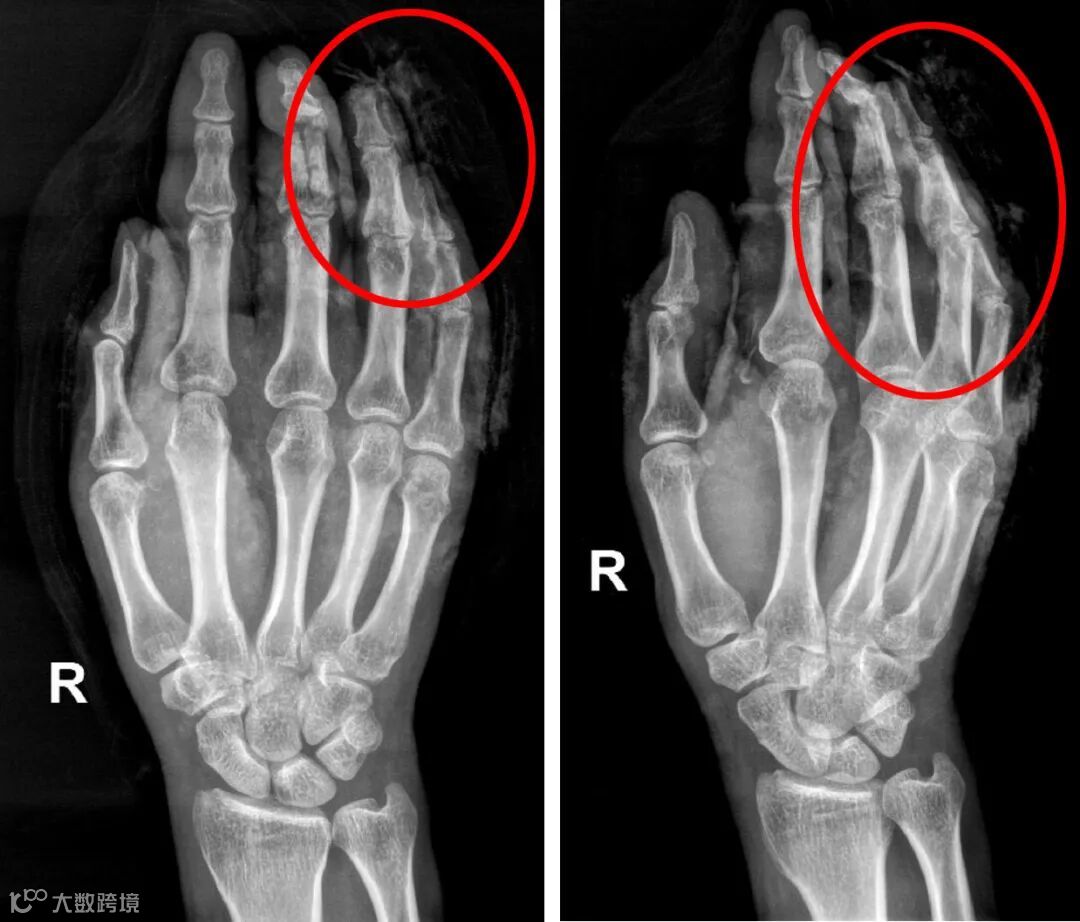

同样是一个多月前右手受伤的高师傅由于伤势较重,还在创伤手外骨科住院治疗,高师傅工作时右手不慎卷入机器的传送带,经拍片检查发现右中指中、远节指骨骨折,右环指远节指骨骨折。去年12月29日21时许,覃育接主刀,王大鹏、韦东江配合为其进行急诊手术,右中指中节指骨骨折复位克氏针内固定,血管、神经探查修复,近节指间关节韧带重建,环指残端修整,食指清创缝合术。从当晚21:50一直到次日凌晨1:15,手术接近3个半小时。